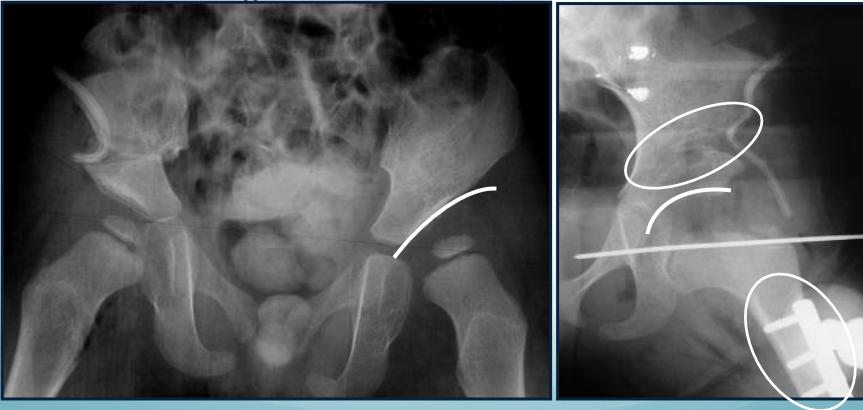

18-24 Months of Age

- Surgical intervention: Open reduction with possible acetabuloplasty

Above 2 Years of Age

- Comprehensive surgical approach:

- Open reduction

- Acetabuloplasty

- Femoral shortening